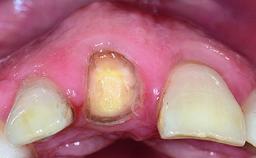

Replacement of a Failing Restored Upper Right Central Incisor, Ridge Preservation and Early Placement of an RC Bone Level Implant

A 23-year-old female, healthy and non-smoking patient had had tooth 11 temporarily restored following a trauma in adolescence. As the patient’s growth had since come to an end and the crown had fractured, she requested an implant-supported restoration of tooth 11. Moreover, the contralateral tooth 21 presented an old composite restoration at the mesial incisal edge. The periodontal tissues were healthy with periodontal probing depth values below 3 mm, but some inflammation was observed around the semi-submerged root of tooth 11.

Bone Volume Deficient horizontally, allowing simultaneous augumentation